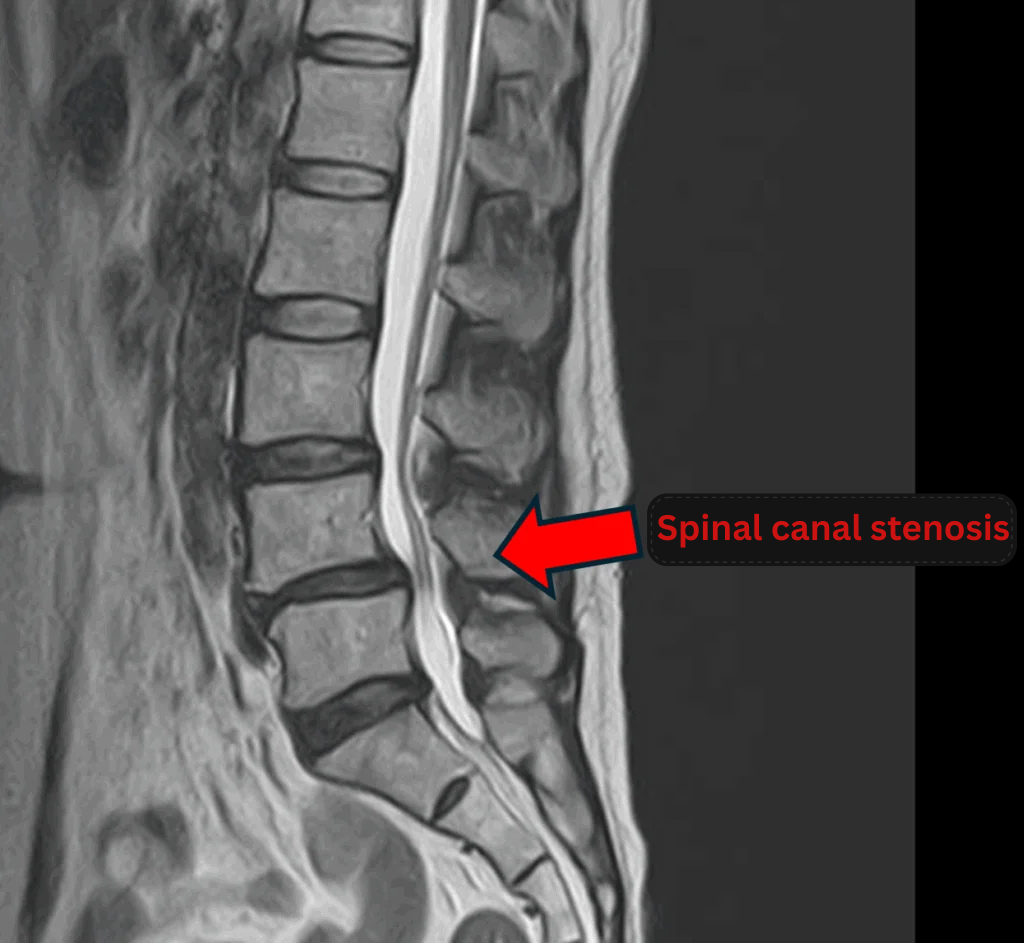

- L3/4, L5/S: Disc degeneration, bulging, foraminal stenosis

- L4/5: Disc degeneration, bulging, foraminal stenosis, spinal canal stenosis

The above findings were also observed on the imaging.

These findings indicate that compression caused by disc changes at L3/4, L4/5, and L5/S is the most likely source of the patient’s symptoms.